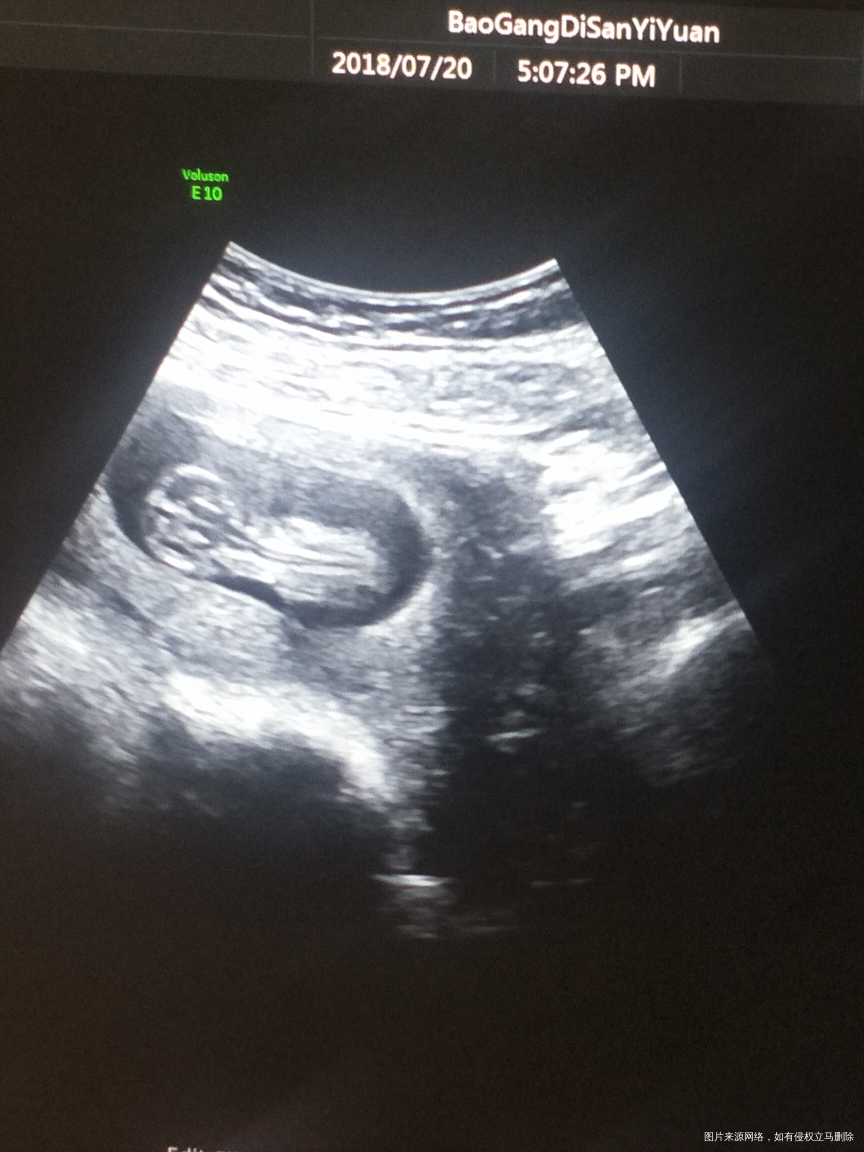

怀孕12周,医生让做NT检查,我们亲亲的大宝就是不配合,不是趴着,就是侧着,正着还要偏一偏,妈妈带你已经去了3天医院了,这个淘气的宝宝,真是拿你没办法!